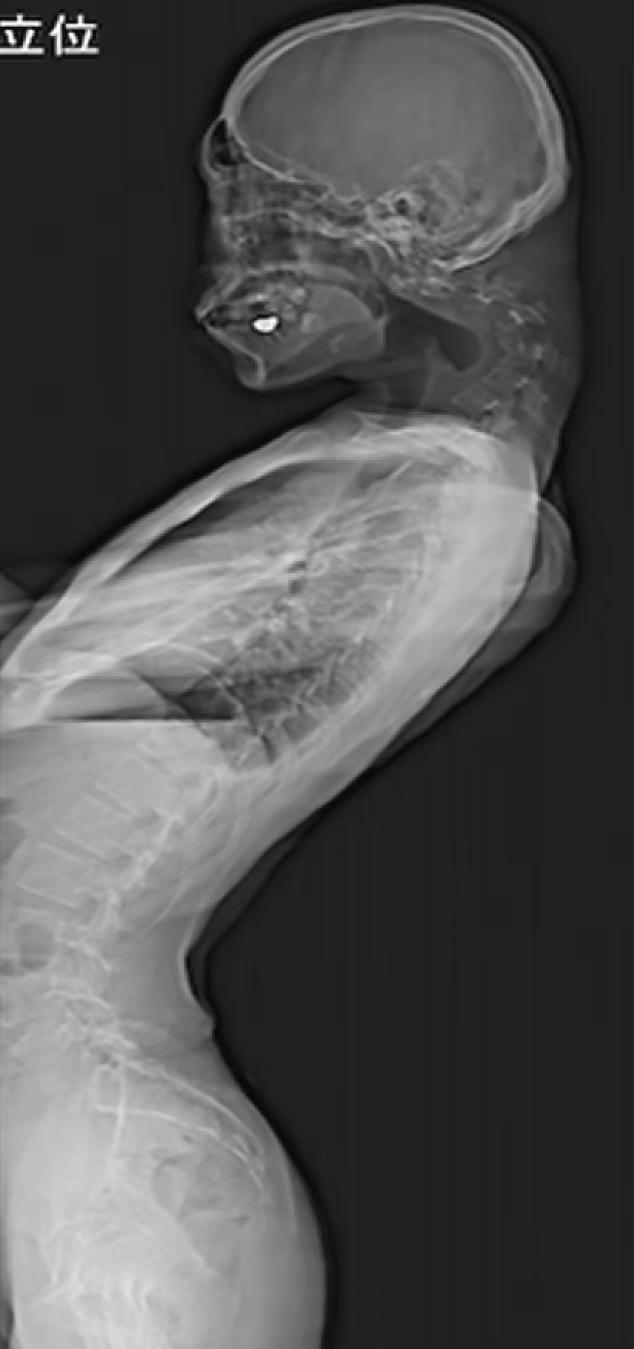

日本一名25歲男子長期低頭玩手機遊戲導致嚴重垂頭症,頸椎向前90度彎曲。(互聯網)

英國《每日郵報》稱,這宗恐怖「垂頭症」(dropped head syndrome)病例於2023年在整形外科期刊JOS Case Reports刊登,X光片可見患者的頸椎明顯90度彎曲,那名男患者頭向前垂,後頸有一角型物體凸出。報道指,患者幼時活潑開朗,但青少年時期遭欺凌變成宅男,退學後躲在房裡數年。他在房間裡只低頭玩手機遊戲,結果導致嚴重垂頭症。除了外觀問題,該男子嚴重頸痛長達半年,也開始抬不起頭,加上吞嚥困難、體重暴降,最終尋求治療。